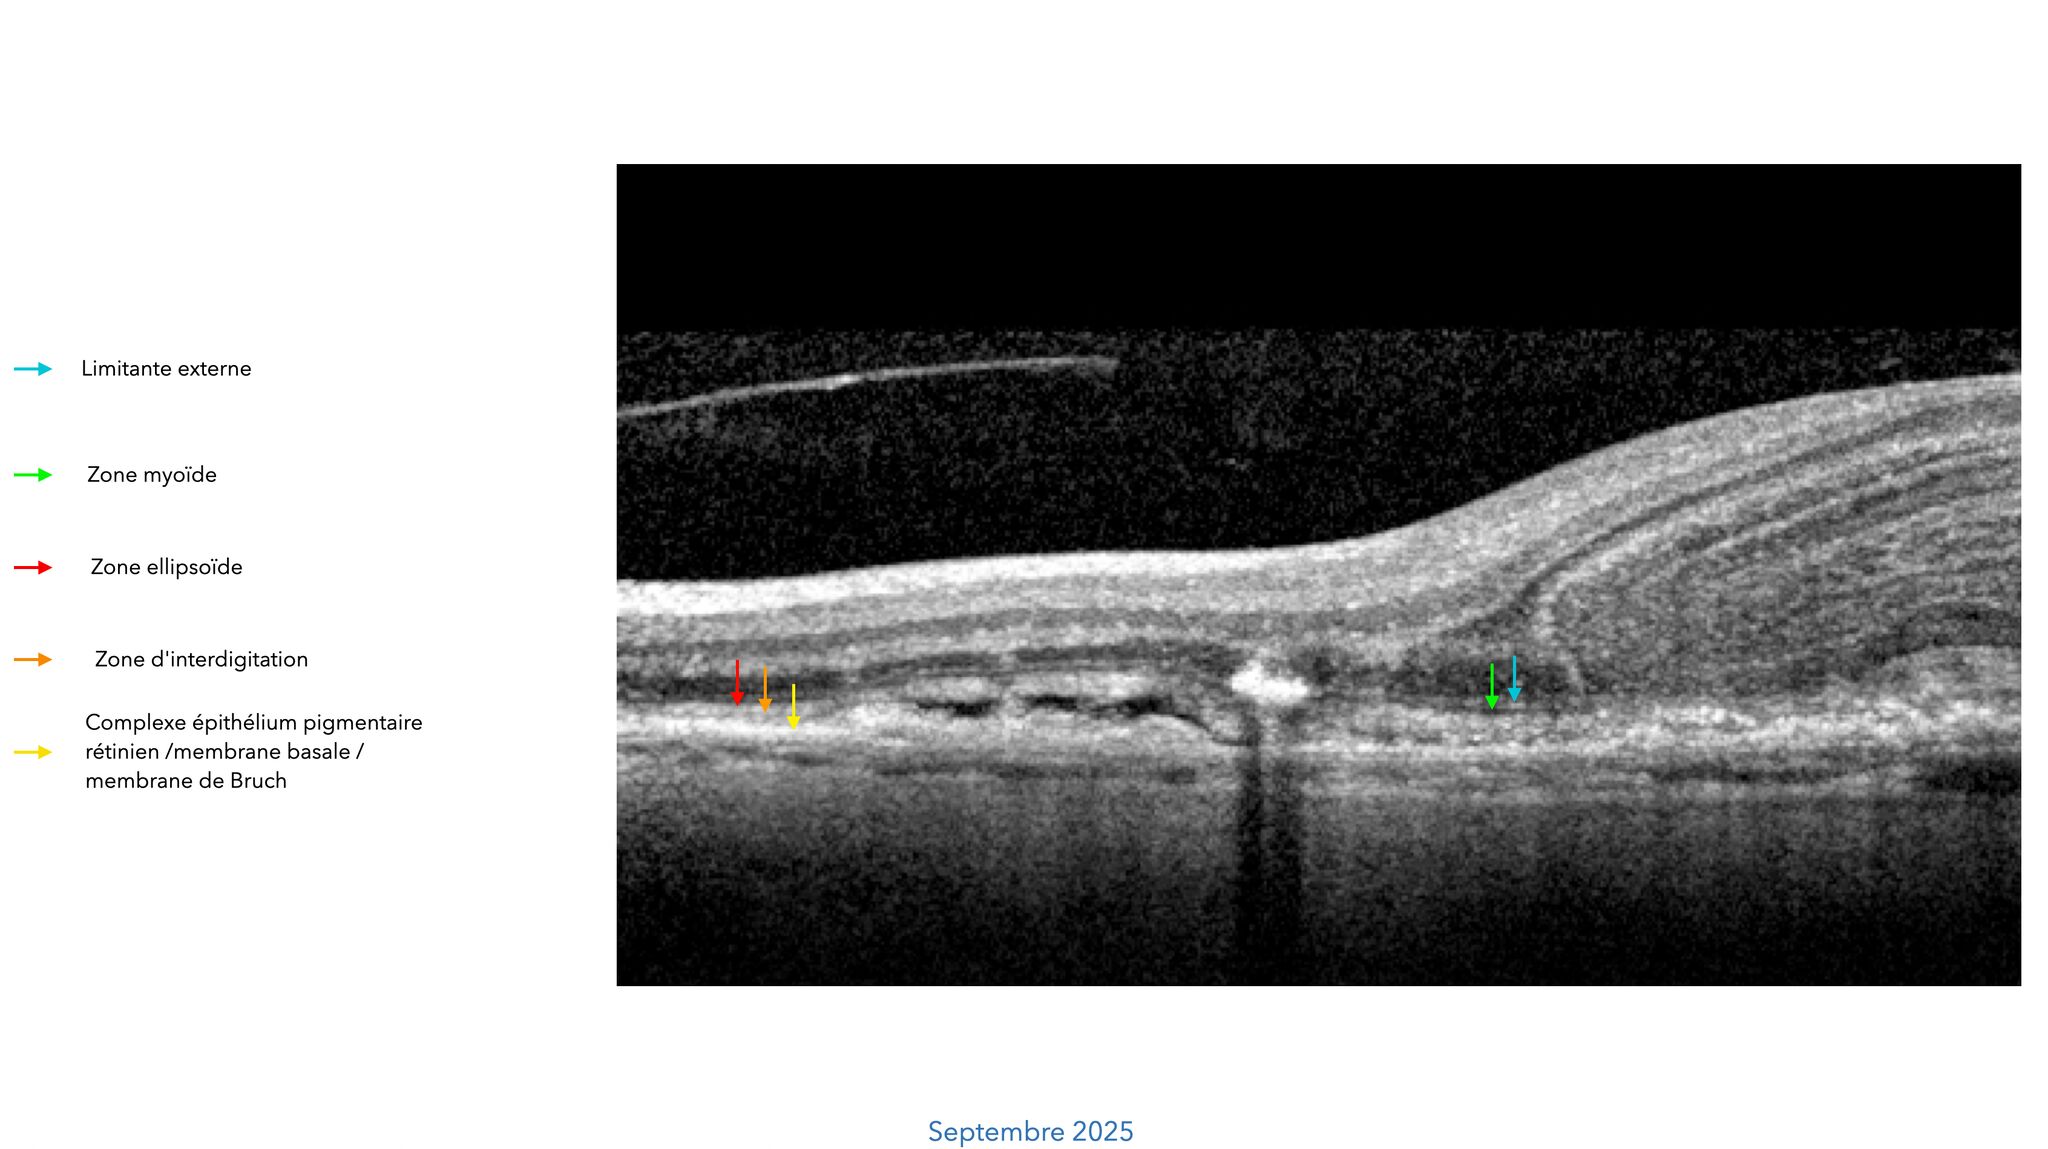

✚ En OCT, on observe un espace kystique intrarétinien, de forme dôme, situé au niveau de la rétine externe.

Il est secondaire à une scission de la zone myoïde, avec :

• une bande granulaire hyperréflective constituant la frontière antérieure

• une ligne d’épaisseur et de réflectivité variables, correspondant à la continuité de la zone ellipsoïde, formant la frontière postérieure.

✚ Ce signe OCT porte le nom de BALAD (Bacillary Layer Detachment).